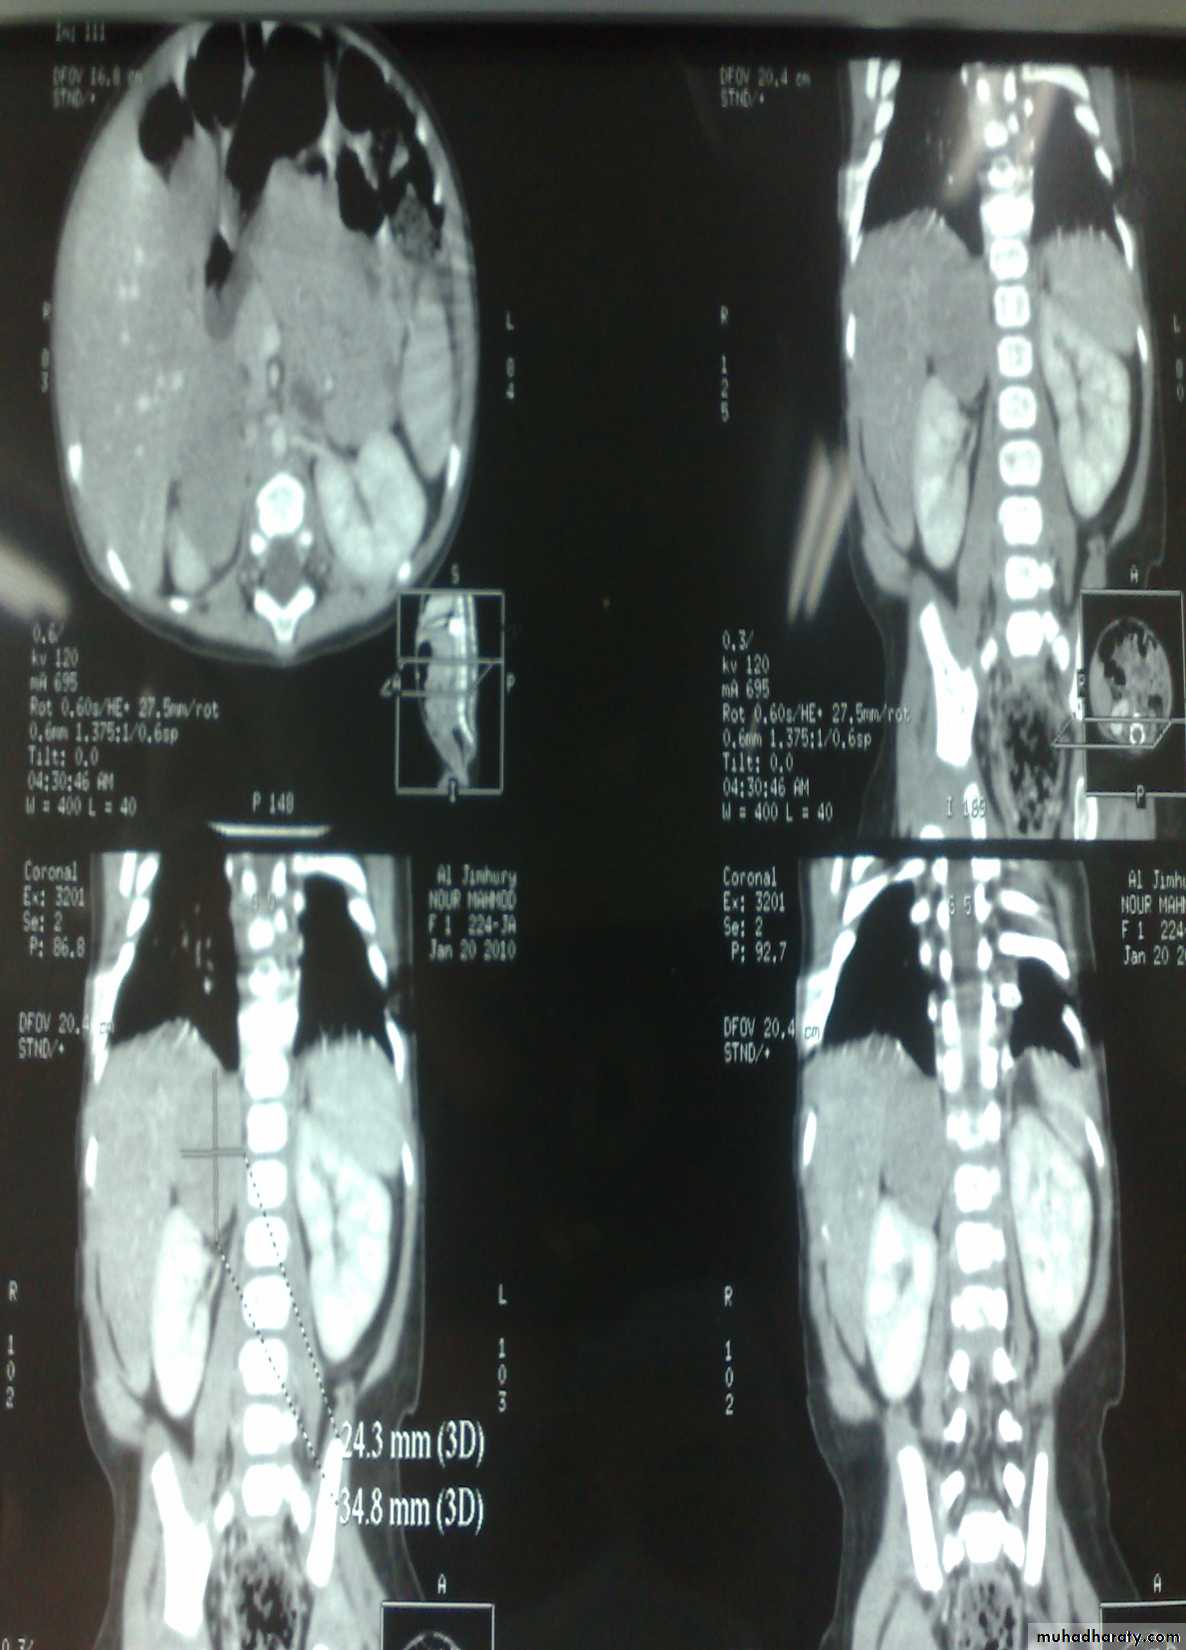

The Child with an Abdominal Mass

5 years child, presented with mass in the flank.

Dx: nephroblastomaDDx of mass in the flank:

1- Wilms tumor2- Neuroblastoma

3- Neglected PUJ obstruction

Presentation:

1- Mass2- hematuria

3- hypertension(1/3pt)

4-Incidental finding

Treatment by surgery remove the kidney + chemotherapy

The most common of pediatric renal tumor is Wilms tumor(second is neuroblastoma) (third is lymphoma non-hogkins),Neuroblastoma in the adrenal gland